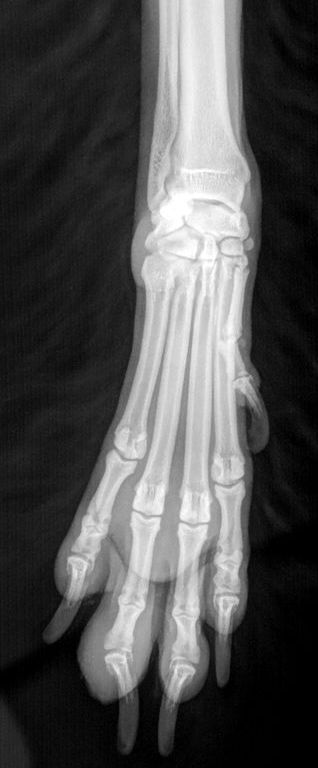

Rechte Vorderpfote

Pfote